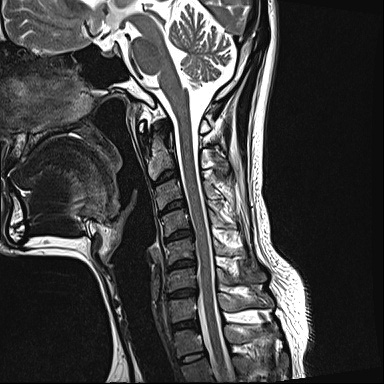

Ű 177 64 40 ()ijħ ڸǥغ ǥغ ϱ ȣϴ 1C.ٸǷ 6C.ڸ 6C.ھ Ḳ 6C.ڻ ()ũ( ߰Ż) ڸ(߹) ĿCڸ(ĸ) Ը ũ(߰Ż)ġ, , Ḳ ġ Ǵ ġ ()ijħ ڸǥغ ǥغ ϰ ߴ ġ 2008~2011 ð ɾƼ ǻ ۾ Ҷ, Ʈ , ȸ ϰ, . 2011 4 : 6,7 ߰Ż , ڸ ó ļ ַ ġ . ü, ߳, ѹ, ũ, ֻġ ġ غ ȿ ġ ġᰡ Ұ Ǵϰ ֿ 3ȸ ƮĪ ణ ȣ. 2014 5 20 濡 ħ ڱ ϰ · ư. (ֱ ϰ, Ʈ ϰ ) а ũ ִ ֺ, Ʒ κп δֻ 1ȸ ̰, ణ . ûϸ鼭 ȸԲ ϴ ûϰ ߽ϴ. Ϻϰ ȸ ּ. mriԴϴ. |